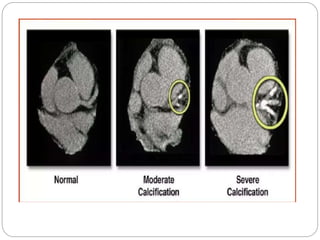

 Vascular calcification, the pathogenic and process of ectopic bone production,

specifically was shown to strongly correlate with degree of atherosclerosis (both

calcified and noncalcified)

 These associations, combined with the radio-opaque appearance of calcium

hydroxyappatite on CT images, have led to extensive investigation of the

quantification, or scoring, of coronary artery calcium (CAC).